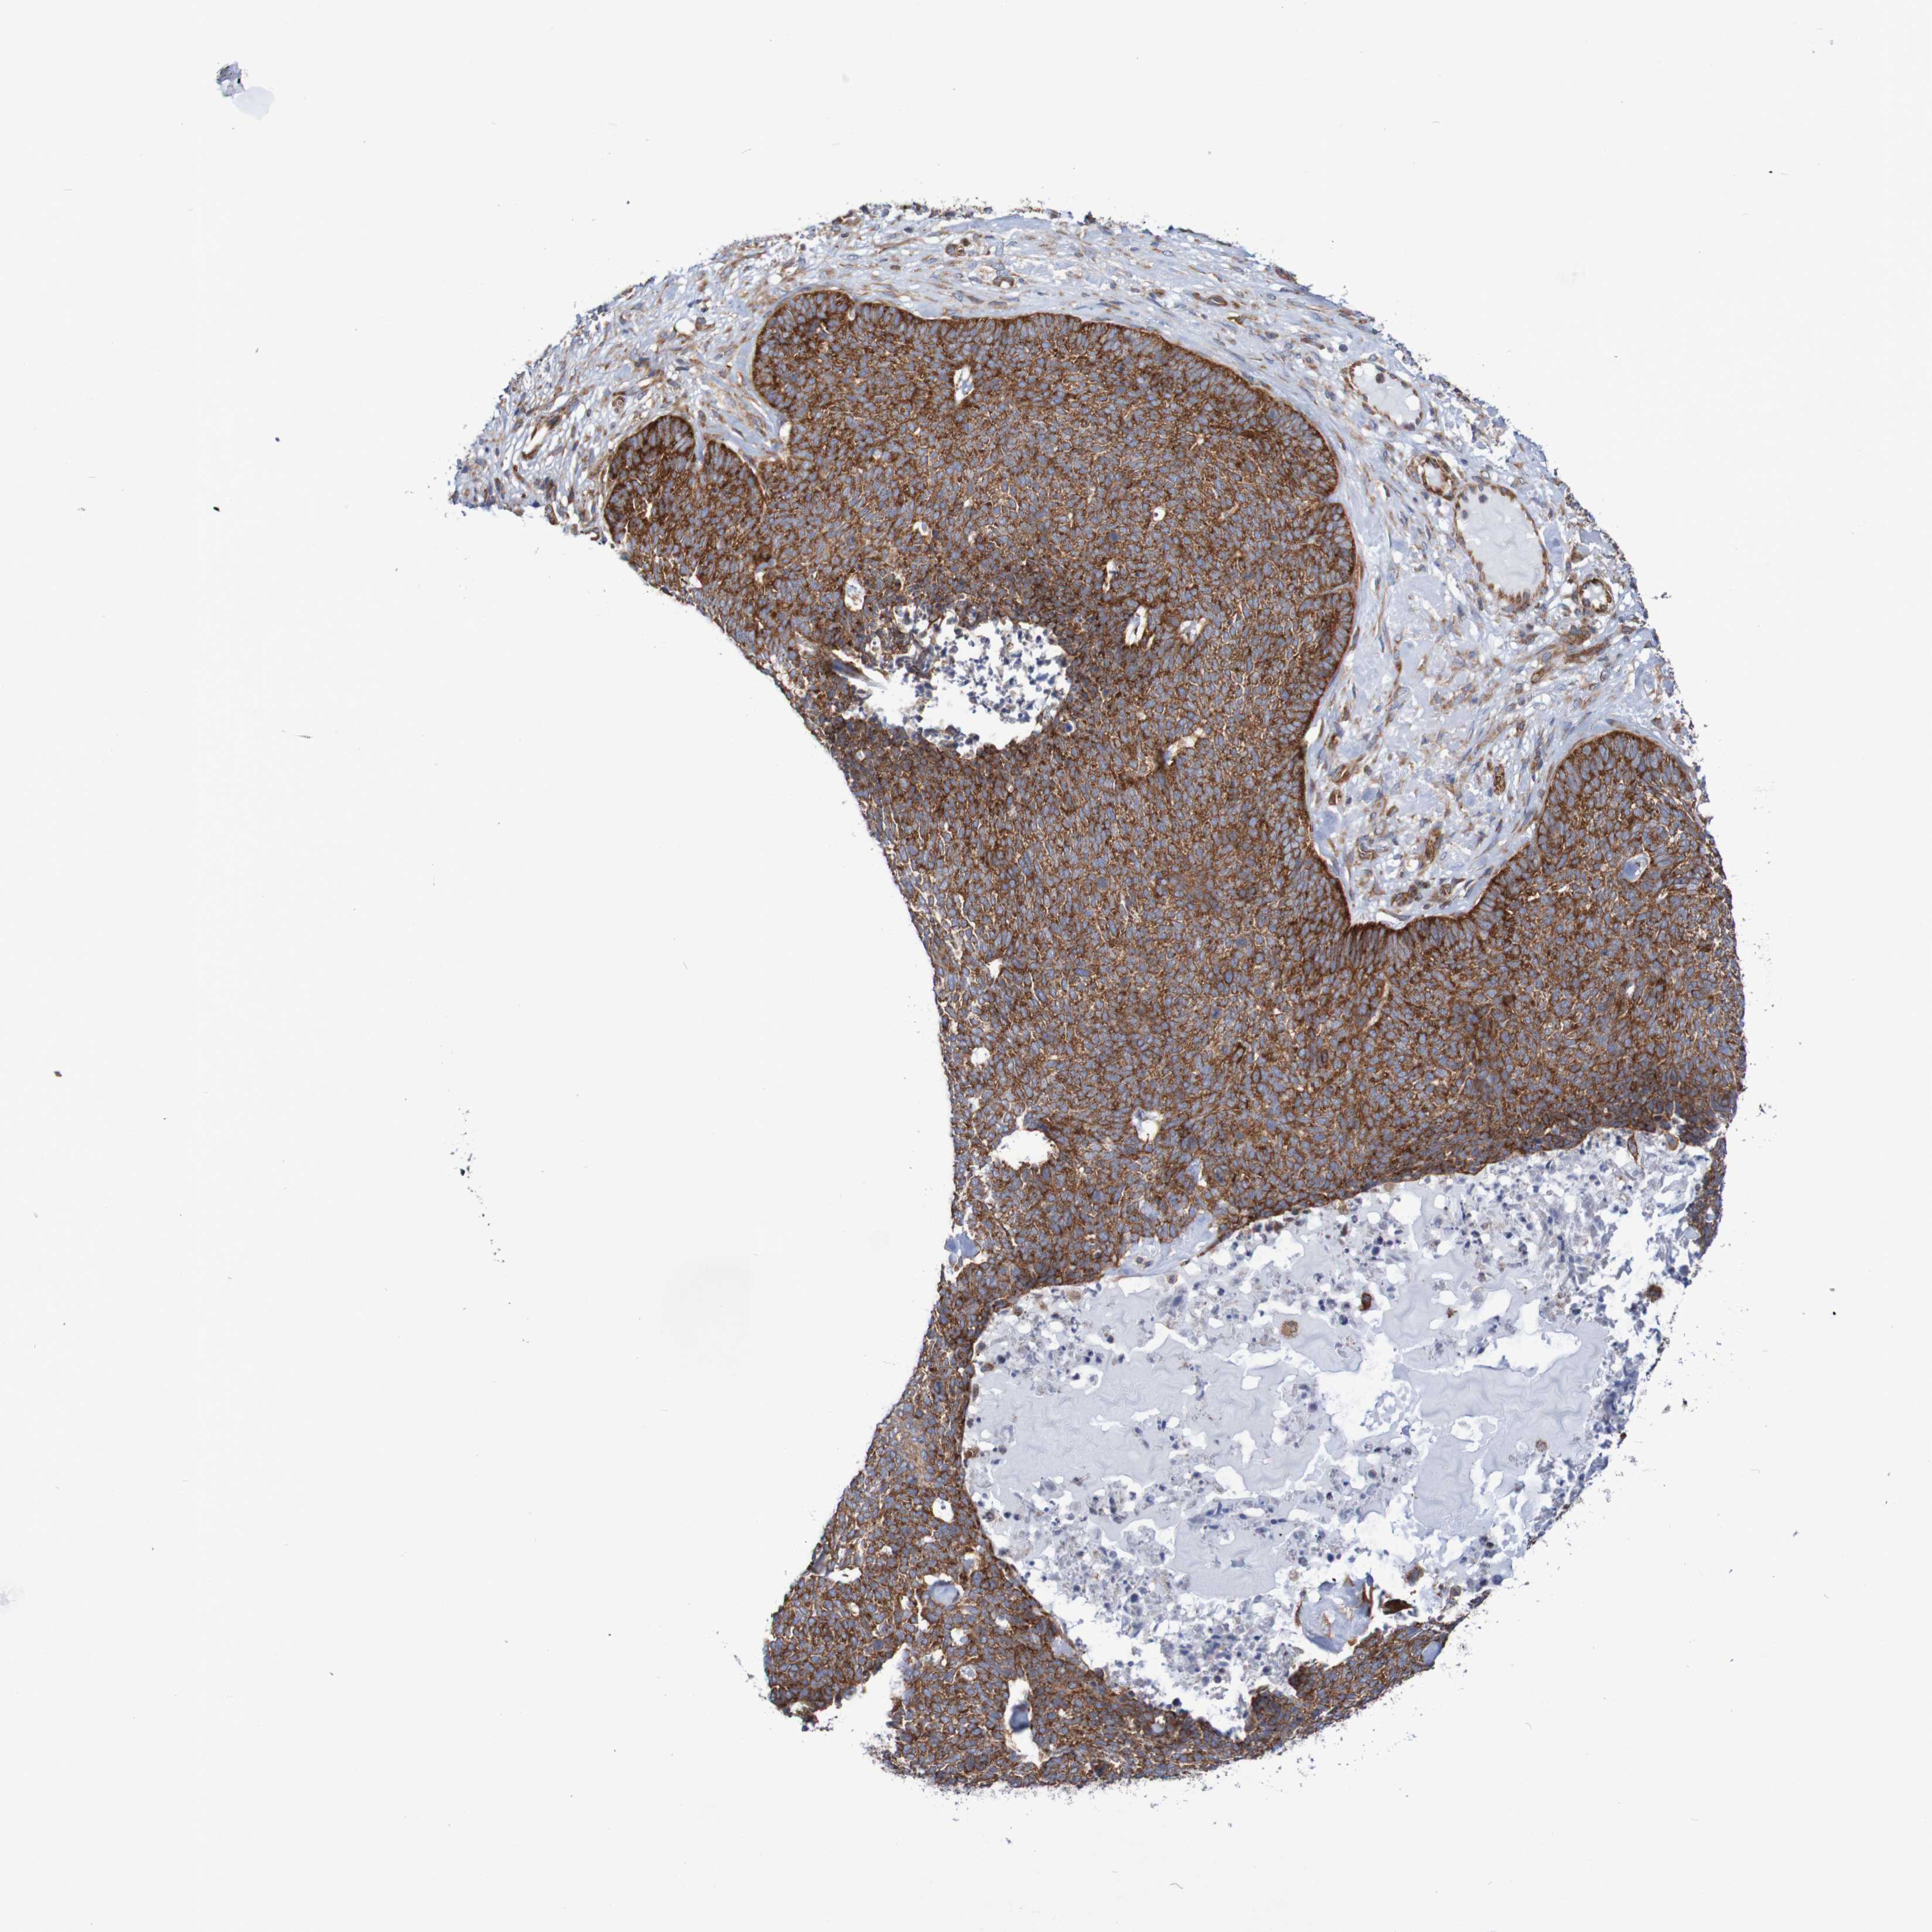

SKIN CANCER - Protein expressioni

A mouse-over function shows sample information and annotation data. Click on an image to view it in a full screen mode. Samples can be filtered based on level of antibody staining by selecting one or several of the following categories: high, medium, low and not detected. The assay and annotation is described here.

Each image is clickable and will lead to virtual microscopy that enables deeper exploration of all samples and also displays staining intensity scores, fraction scores and subcellular localization as well as patient and tissue information for each sample.

Antibody HPA022997

High

Strong

>75%

Location

Basal cell carcinoma